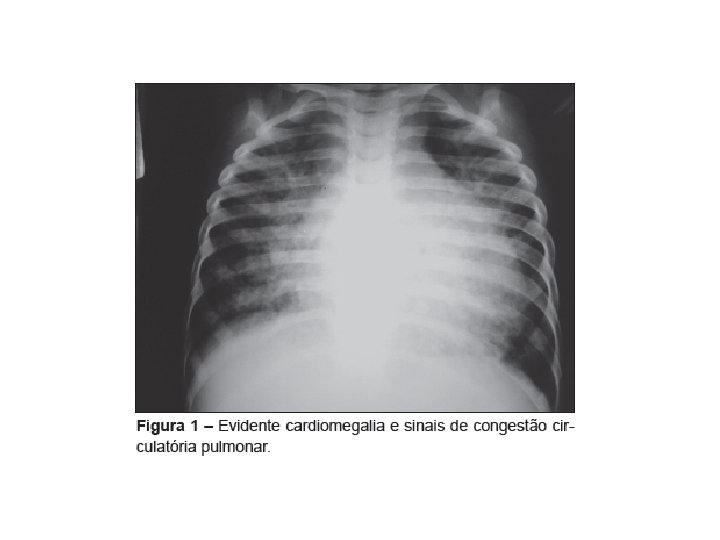

AVALIAÇÃO PROPEDÊUTICA Bioquímica Ø Eletrólitos séricos : Na, K, Ca, Mg Ø Função hepática : AST, ALT, bilirrubinas, albumina, TAP Ø Função renal : uréia, creatinina Ø Função tireoidiana : T 3, T 4, TSH Ø Hemograma Radiografia torácica Índice cardiotorácico aumentado, sinais de crescimento de câmaras e proeminências vasculares, congestão vascular e inversão da trama, infiltrado intersticial e alveolar, “cisurites” , linhas B de Kerley, derrame pleural. Eletrocardiograma Avalia ritmo, sobrecarga de câmaras, áreas de infarto, bloqueios de ramo e bloqueios atrioventriculares. Ecocardiograma Dilatação de câmaras, função ventricular, lesões valvares.

Fatores prognósticos adversos ØGraus II-IV da NYHA ØCapacidade reduzida para exercícios (VO 2 máx. < 10 ml/Kg/min) ØPresença de ritmo de galope (B 3) ØCausa da ICC é a doença arterial coronariana ØCardiomegalia no Rx de tórax ( índice CT>0, 55) ØBloqueio do ramo esquerdo ao ECG de repouso Ø[Na+] plamático < 130 mmol/litro ØNoradrenalina plasmática elevada ØAngiotensina II plasmática elevada ØTaquicardia ventricular, batimentos ventriculares polimóficos Ø Níveis de Hb < 13 mg/dl ou > 17 mg/dl Ø Presença de insuficiência renal crônica

Desafio Paciente de 64 anos, portadora de insuficiência cardíaca estável, está sendo avaliada devido a espisódio de descompensação, caracterizado por crescente dispnéia aos esforços, ortopnéia e ganho de peso de 5, 0 kg. Ao exame físico, pulso de 102 bpm e pressão arterial de 140/85 mm. Hg. Veias jugulares turgidas e pulsáteis. Faz uso de inibidor da ECA e furasemida. Ao estudo radiológico do tórax nota-se uma imagem radiodensa.